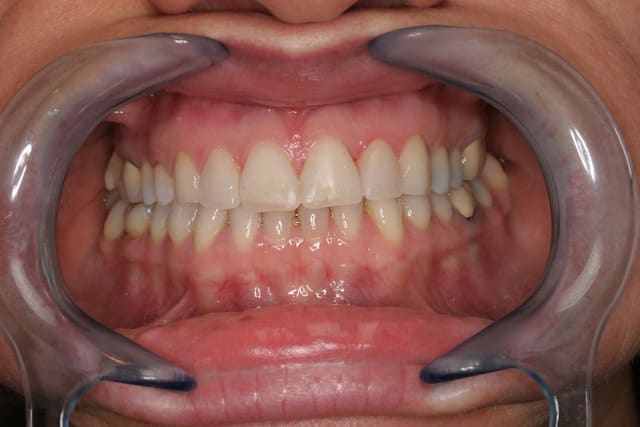

voilà le resultat collé

je suis resté trop supragingival, mais la patiente est très contente (ouf, c'est l'essentiel !)

E carteurs yiazkj - Eugenol

Occlusal jyrk8g - Eugenol